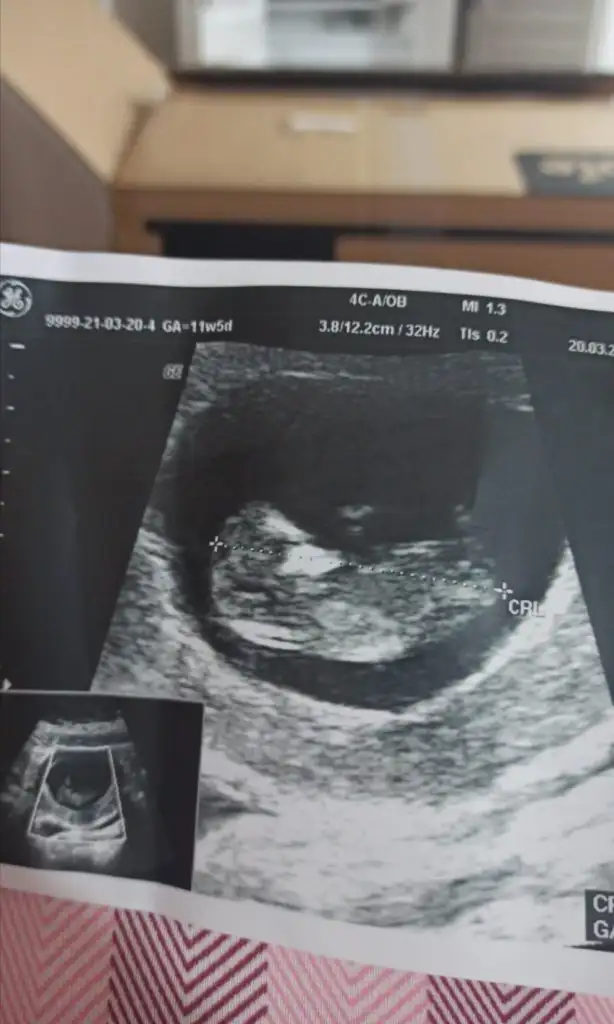

12 haftalıkKac haftalık 11 12 13 haftalar olmalı kız sanki

Dr + getirmiş nubuna görülmüyor tipi kız gibi sanki 11-12 hafta varsa paylaşın